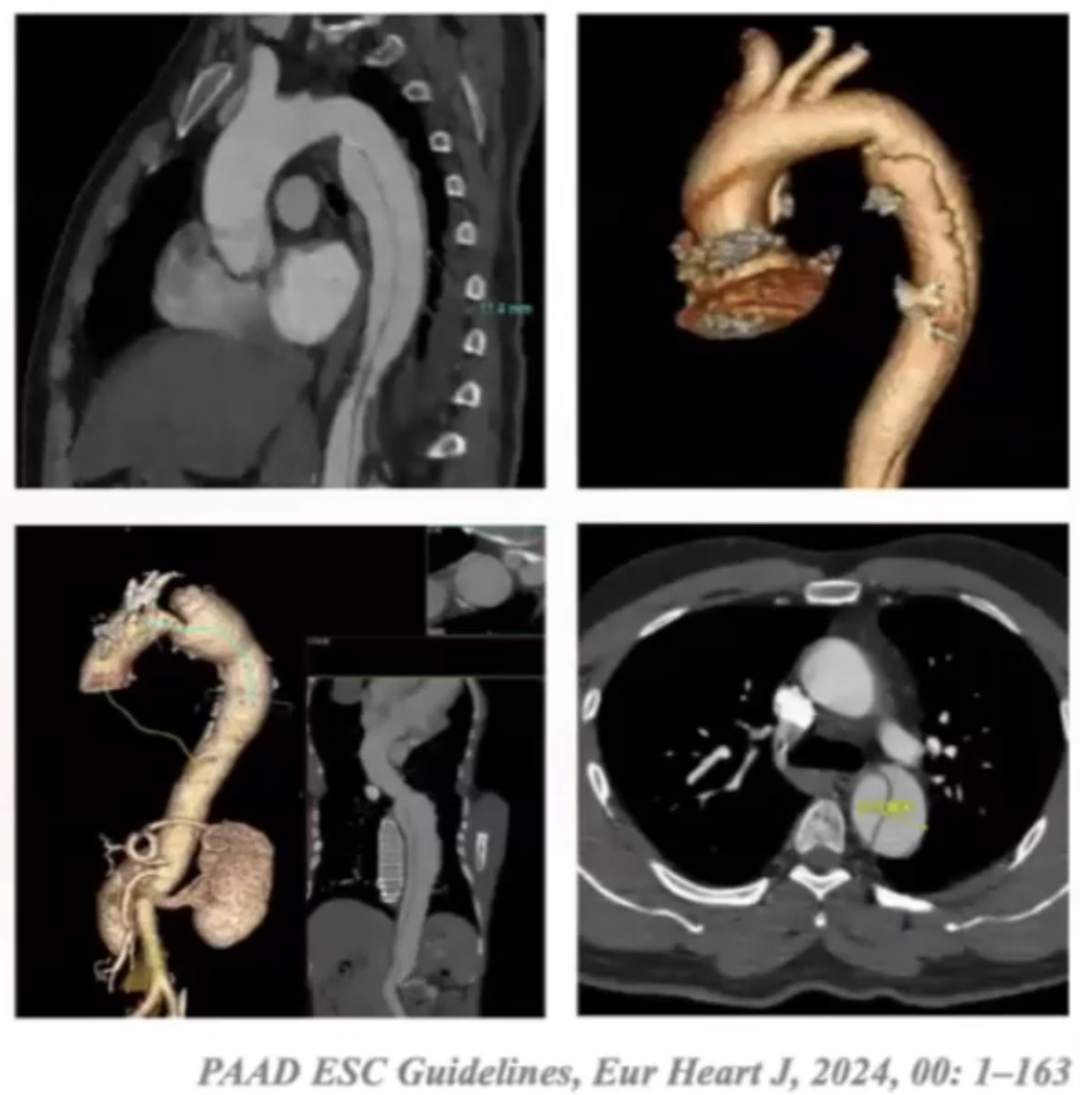

目前对于急性复杂性夹层的治疗,临床已形成较为一致的首选方案。但针对急性非复杂性B型主动脉夹层,腔内治疗(TEVAR)与单纯药物治疗的远期疗效对比仍存在争议。现有指南虽倾向于亚急性期治疗,但相关证据等级有限。在国内临床实践中,急性期接受TEVAR治疗的患者数量反而多于亚急性期。

非复杂型TBAD存在特定的影像学及临床特征。在影像学方面,具备7个关键特征:

① 主动脉直径大于40mm

② 假腔直径大于22mm

③ 第一破口直径大于10mm

④ 小弯侧存在原发破口

⑤ 住院期间全主动脉直径增长超过5mm

⑥ 单纯通过影像学检查发现存在灌注不良的情况

⑦ 出现血性胸腔积液

这些影像学和临床特征对于非复杂型TBAD的诊断、病情评估及后续治疗具有重要意义。